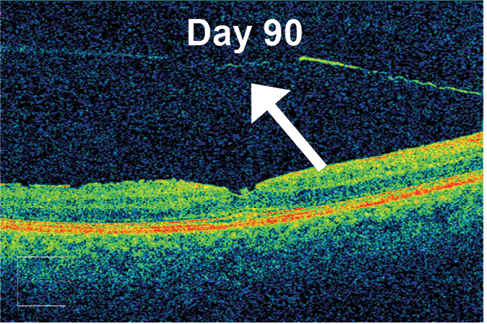

Results from this study suggest an alternative approach to pharmacologic vitreolysis (unpublished data). Although further data analysis is ongoing, roughly 65% of patients in the highest dose group in this dose-ranging study achieved the study’s primary endpoint of complete VMT release on OCT by day 90. Importantly, ALG-1001 was well tolerated, and no significant safety issues were seen. Injections of ALG-1001 can be repeated, and in this study up to three monthly injections were allowed. In patients in the 3.2-mg group (the highest dose tested), an average of 1.6 doses were required to achieve VMT release (Figure).

Figure. Example of VMT release in a patient at baseline (TOP) and after 90 days of follow-up after an injection of ALG-1001 3.2 mg (BOTTOM). Note the full separation of the posterior hyaloid membrane from the underlying retinal interface.